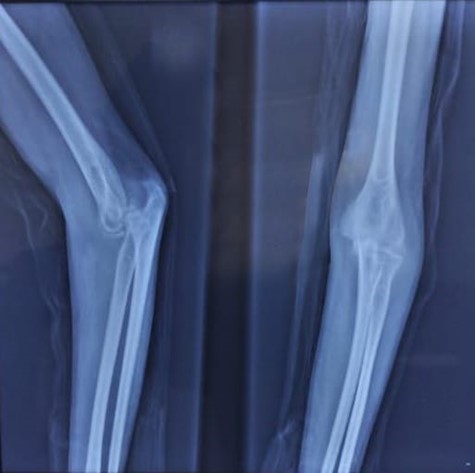

An X-ray of the elbow with AP and lateral views as seen in Figure 1 revealed a posterior dislocation of the elbow with heterotopic ossifications. The patient was hospitalised and pre-operative bloodwork was done in preparation for a surgical reduction.

Figure 1: posterior elbow dislocation with osteophytes in the olecranon fossa and trochlear notch